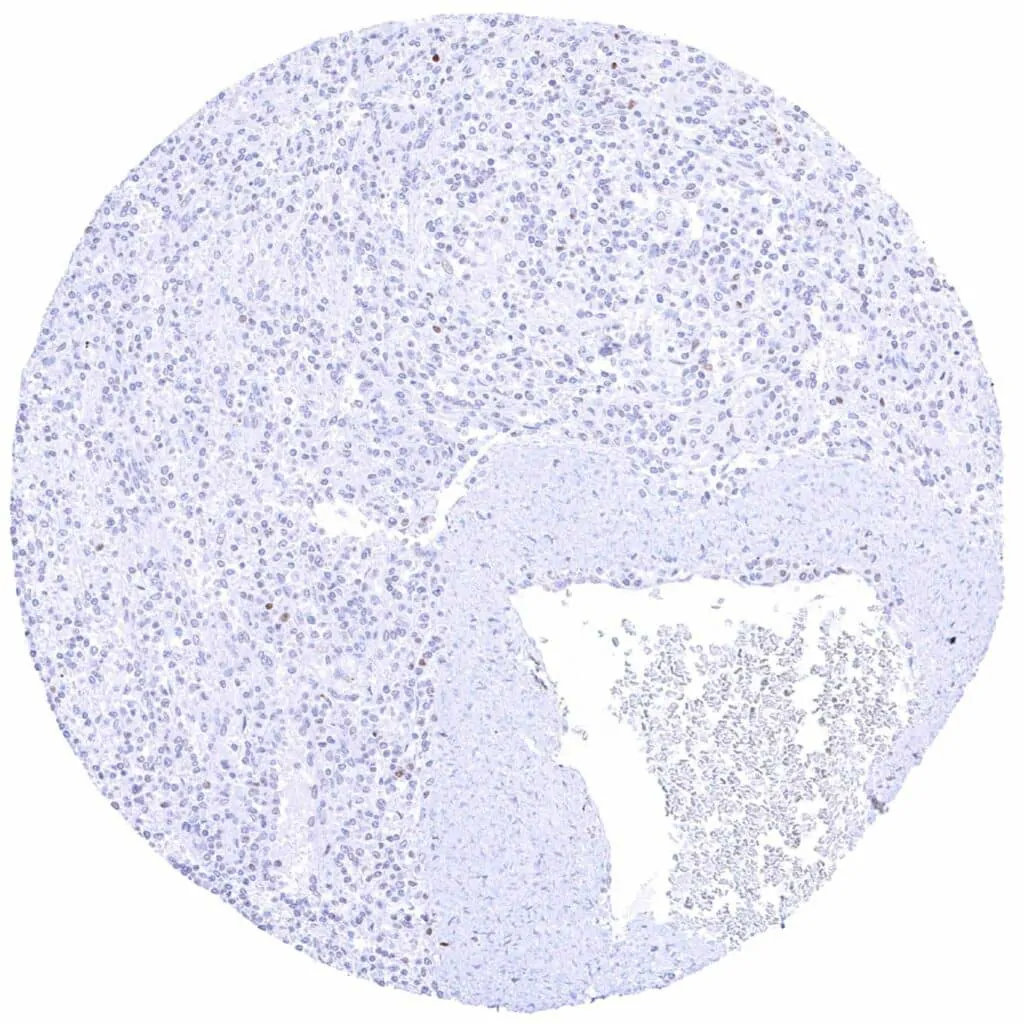

Lymph node – Weak Cyclin E1 staining of only a small fraction of cells